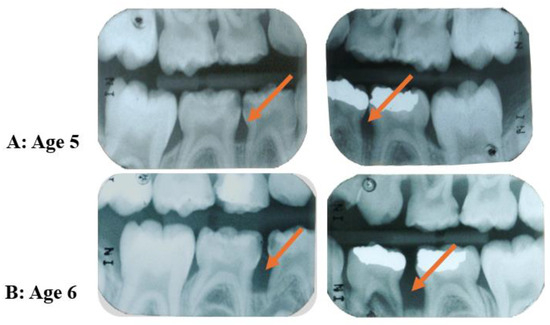

Figure 6.

Retrospective evaluation of radiographs of a sibling of a C-MIP patient. Childhood radiographic records show initial bone loss at the first primary molars at five years old (A). The disease progressed fast and spread to the second primary molars at age 6 (orange arrows) (B). (Source of the image [16]).